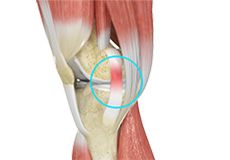

Tendons of the Knee

A tendon is a tissue that attaches a muscle to a bone. The quadriceps muscles of the knee meet just above the patella and attach to it through a tendon called the quadriceps tendon. The patella further attaches to the tibia through a tendon called the patella tendon. The quadriceps muscle, quadriceps tendon, and patellar tendon all work together to straighten the knee. Similarly, the hamstring muscles at the back of the leg are attached to the knee joint with the hamstring tendon.